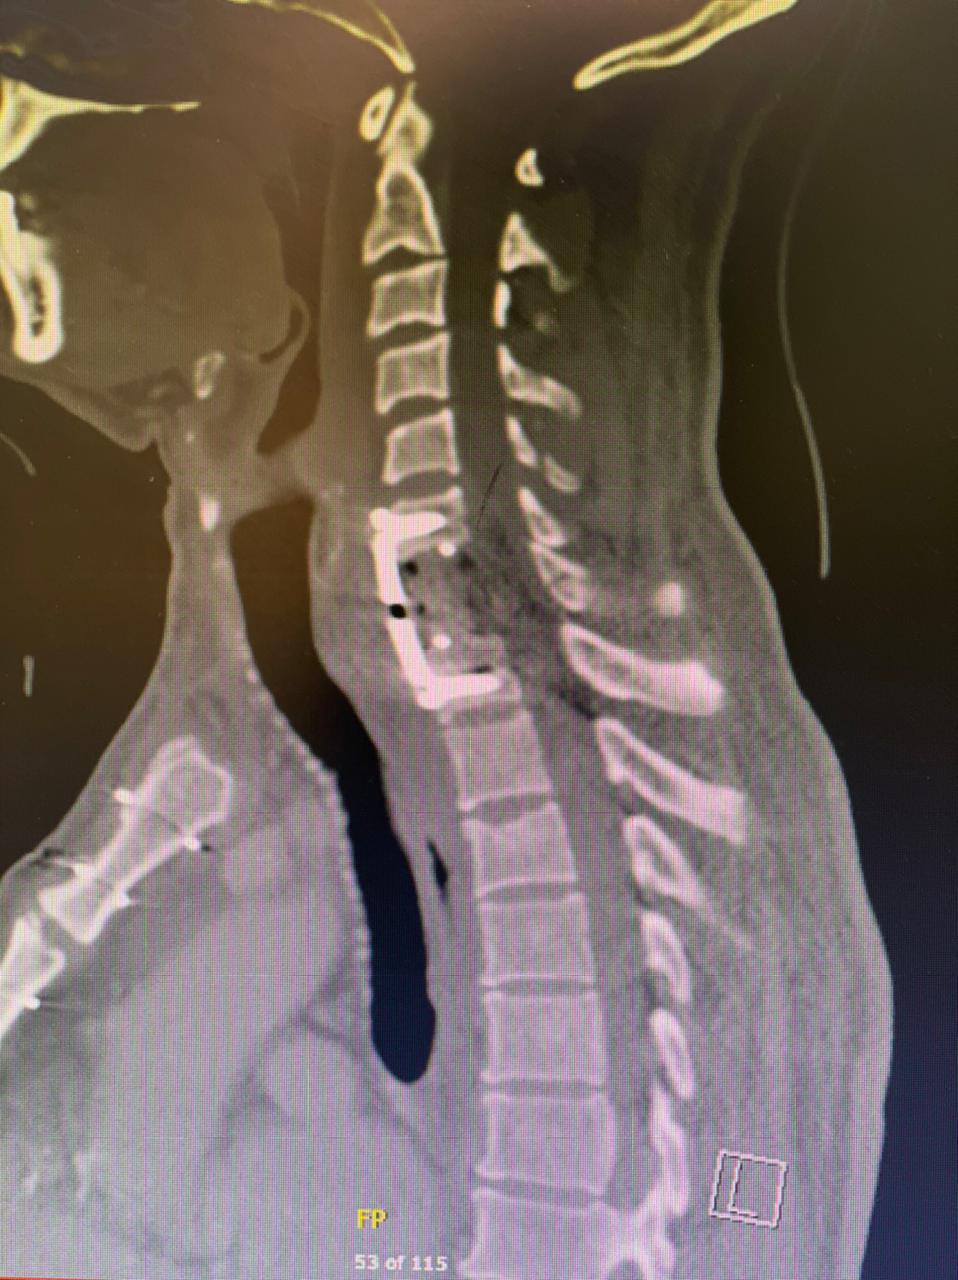

نجاح عملية نوعية في مستشفى الملك فهد لإستبدال الفقرة العنقية بالفقرة الإصطناعية

تمكن بفضل الله فريق طبي متخصص في مستشفى الملك فهد التخصصي ببريدة من إجراء عملية جراحية نوعية لمصاب في حادث مروري حيث تبين بعد إجراء الفحوصات السريرية والاشعاعية اللازمة وحود كسر مضاعف بالفقرة السابعة في العنق (C7) وهى تعتبر من اخطر الفقرات بحكم موقعها ومكانها بين فقرات العنق والصدر وقد كان يشكو من تنميل وضعف في الأطراف والتي ربما مضاعفاتها تؤدي لشلل رباعي لاسمح الله .

وكانت العملية عبارة عن جراحة استبدال الفقرة العنقية بالفقرة الإصطناعية ( ACCF : Anterior cervical corpectomy and fusion ) حيث يتم خلال هذه العملية إزالة الفقرة المتأثرة بفقرة أخرى جديدة صناعية مما يجعل الأمر حساس ودقيق جدا بحكم قربها من الحبل الشوكي والأعصاب المسؤولة عن الحركة، ولله الحمد بعد توفيق الله ثم جهود الفريق تم التدخل الجراحي وإجراء العملية بكل دقة وقد تكللت بالنجاح ولله الحمد.